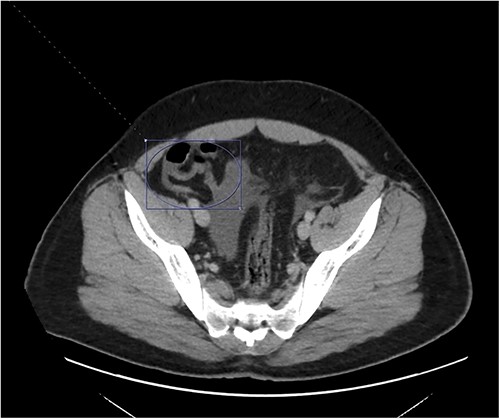

Thrombosis can be seen extending into the mesenteric venous system as well as the intrahepatic portal veins; associated mesenteritis and abdominal ascites (not well visualized) are also seen.

Patient was admitted to the surgical service and started on broad-spectrum IV antibiotics (piperacillin–tazobactam) and was made nil per os. He was resuscitated intravenously with 2 l of crystalloid. Given the thrombosis of his PV and SMV, the patient was initiated on systemic anticoagulation with IV heparin which achieved therapeutic dosing within 24 hours. Over the course of the next few days, his abdominal pain and tachycardia improved. Interval CT abdomen/pelvis scan 5 days from presentation demonstrated progression of the thrombus to involve lobar, segmental, and subsegmental portal venous branches as well as the splenic vein distal to the portosplenic confluence (Fig. 2).